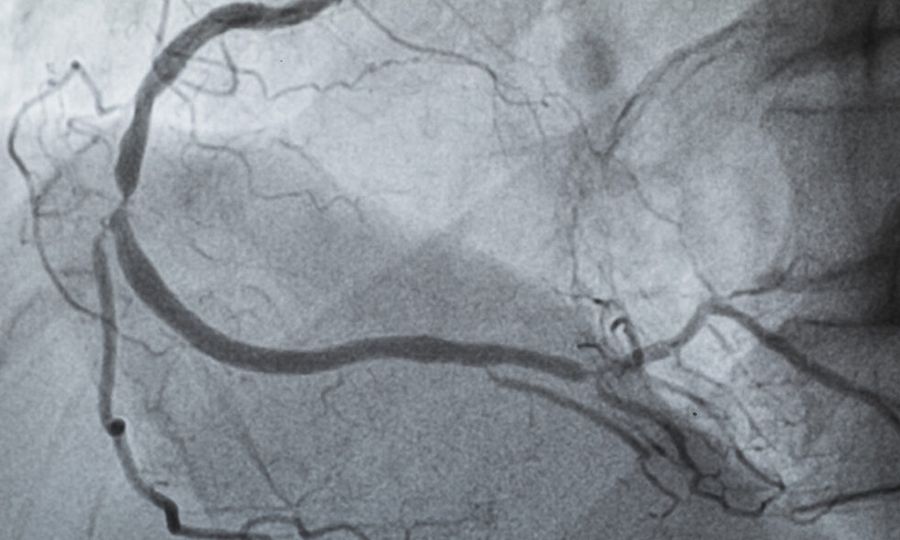

Οι γιατροί συνήθως ελέγχουν την ύπαρξη απόφραξης στις αρτηρίες της καρδιάς με τη βοήθεια της στεφανιογραφίας, μιας επεμβατικής εξέτασης η οποία χρησιμοποιεί χρωστική ουσία και ακτινογραφίες. Κατά την τελευταία δεκαετία, μεγάλες ευρωπαϊκές μελέτες διαπίστωσαν ότι τα ποσοστά στένωσης στα στεφανιαία αγγεία έχουν μειωθεί κατά περίπου 30% τόσο στους άνδρες όσο και στις γυναίκες με συμπτώματα στεφανιαίας νόσου. «Έχουμε δει παρόμοιες τάσεις στα μητρώα της Υπηρεσίας Βετεράνων, της Mayo Clinic και του δικού μας Mass General Brigham, εδώ και περίπου 15 χρόνια», λέει ο δρ DiCarli, ο οποίος είναι εκτελεστικός διευθυντής καρδιαγγειακής απεικόνισης στο Brigham and Women’s Hospital. Αντί για επεμβατικές αγγειογραφίες, στο μητρώο του Mass General Brigham καταγράφονται αποτελέσματα από μια μη επεμβατική απεικονιστική εξέταση που ονομάζεται αξονική στεφανιογραφία. Τα ευρήματα αυτού του μητρώου, το οποίο περιλαμβάνει άτομα κάτω των 65 ετών (αντίθετα με άλλα μητρώα, τα οποία περιλαμβάνουν κυρίως ηλικιωμένους), έδειξαν επίσηςμείωση της αποφρακτικής στεφανιαίας νόσου κατά 30% έως 40% στην πάροδο του χρόνου.